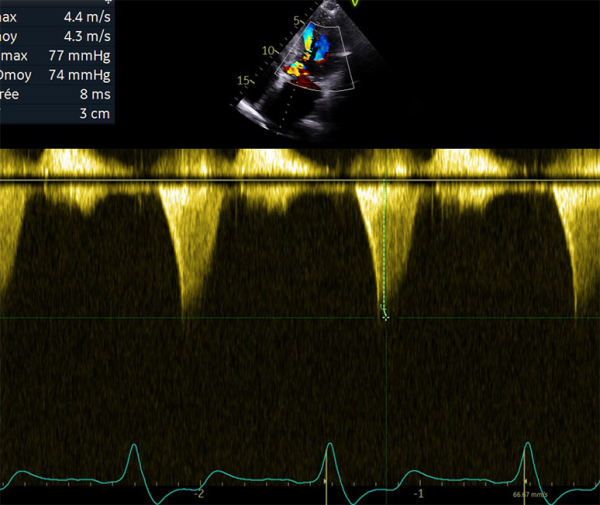

Figure 2 : flux Doppler continu trans-aortique d’obstruction

- Patient de 40 ans avec une CMH sarcomérique (mutation HTZ MYBPC3) avec épaisseur maximale en antéro-septo-basal à 33mm en IRM, associée à une obstruction sous aortique significative (GD max 77 mm Hg au Valsalva). Découverte d’une insuffisance mitrale (IM) sévère mixte organique sur prolapsus de P2 et fonctionnelle sur un SAM (mouvement systolique antérieur de la valve mitrale)